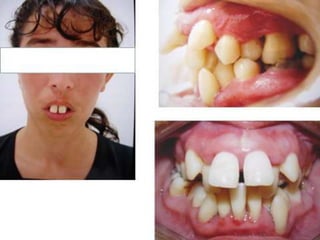

O documento descreve o tratamento de um paciente com incompetência labial, interferência lingual e deglutição atípica ao longo de vários anos, incluindo o uso de placas, remodelação transversal e guias de oclusão para corrigir problemas de alinhamento e contato dental. O paciente continuou com hábitos bucais indesejados apesar dos tratamentos realizados.